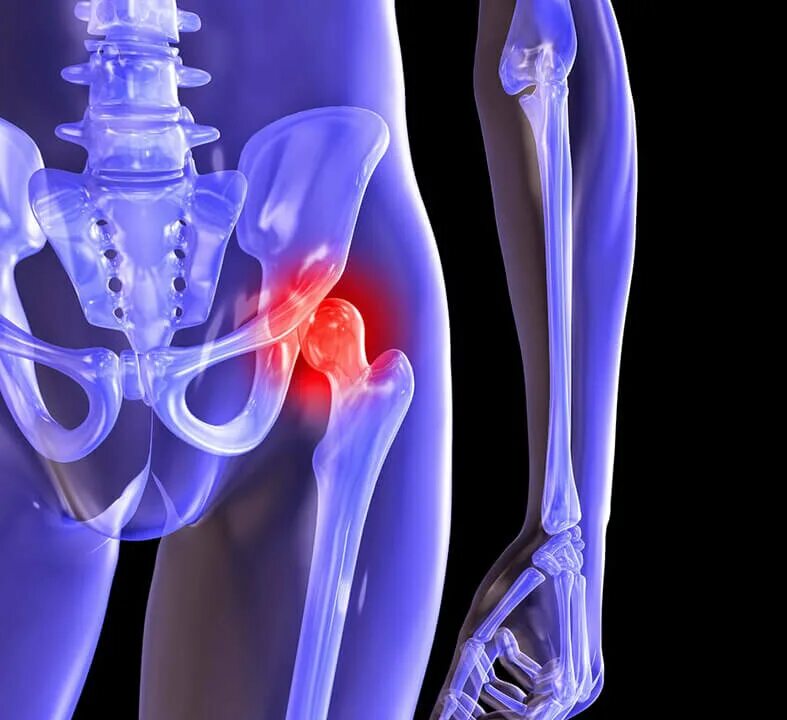

Коксартроз тазобедренного сустава 3